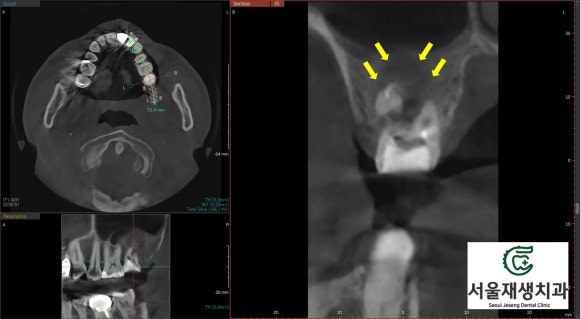

위 사진에서 보시는 바와 같이,

깨끗하고 튼튼하게 신경치료가 마무리 되었습니다.

치료 전후의 평면 엑스레이 사진입니다.